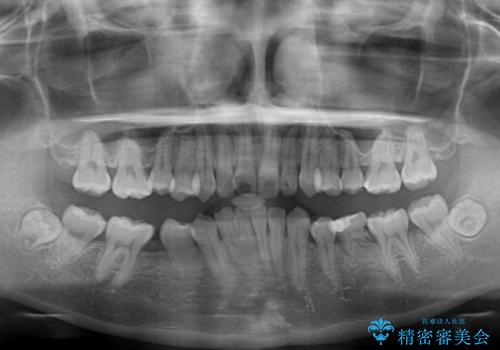

- 後続永久歯の欠損によるスペースと残存乳歯、深い咬み合わせを気にして来院された患者様です。

乳歯を残し、欠損部位のスペースを適正な幅に拡大し、インプラント補綴治療により歯列を整える治療も考えられましたが、ご本人から飛び出している前歯をどうしても引っ込めたいとの要望があったため、残存乳歯ならびに上顎左右第二小臼歯を抜歯して、歯列を整えることとしました。

上下臼歯の咬み合わせ改善には補助装置を、深い咬み合わせ改善にはユーティリティーアーチを活用し、ワイヤー装置にて矯正治療を行うこととしました。